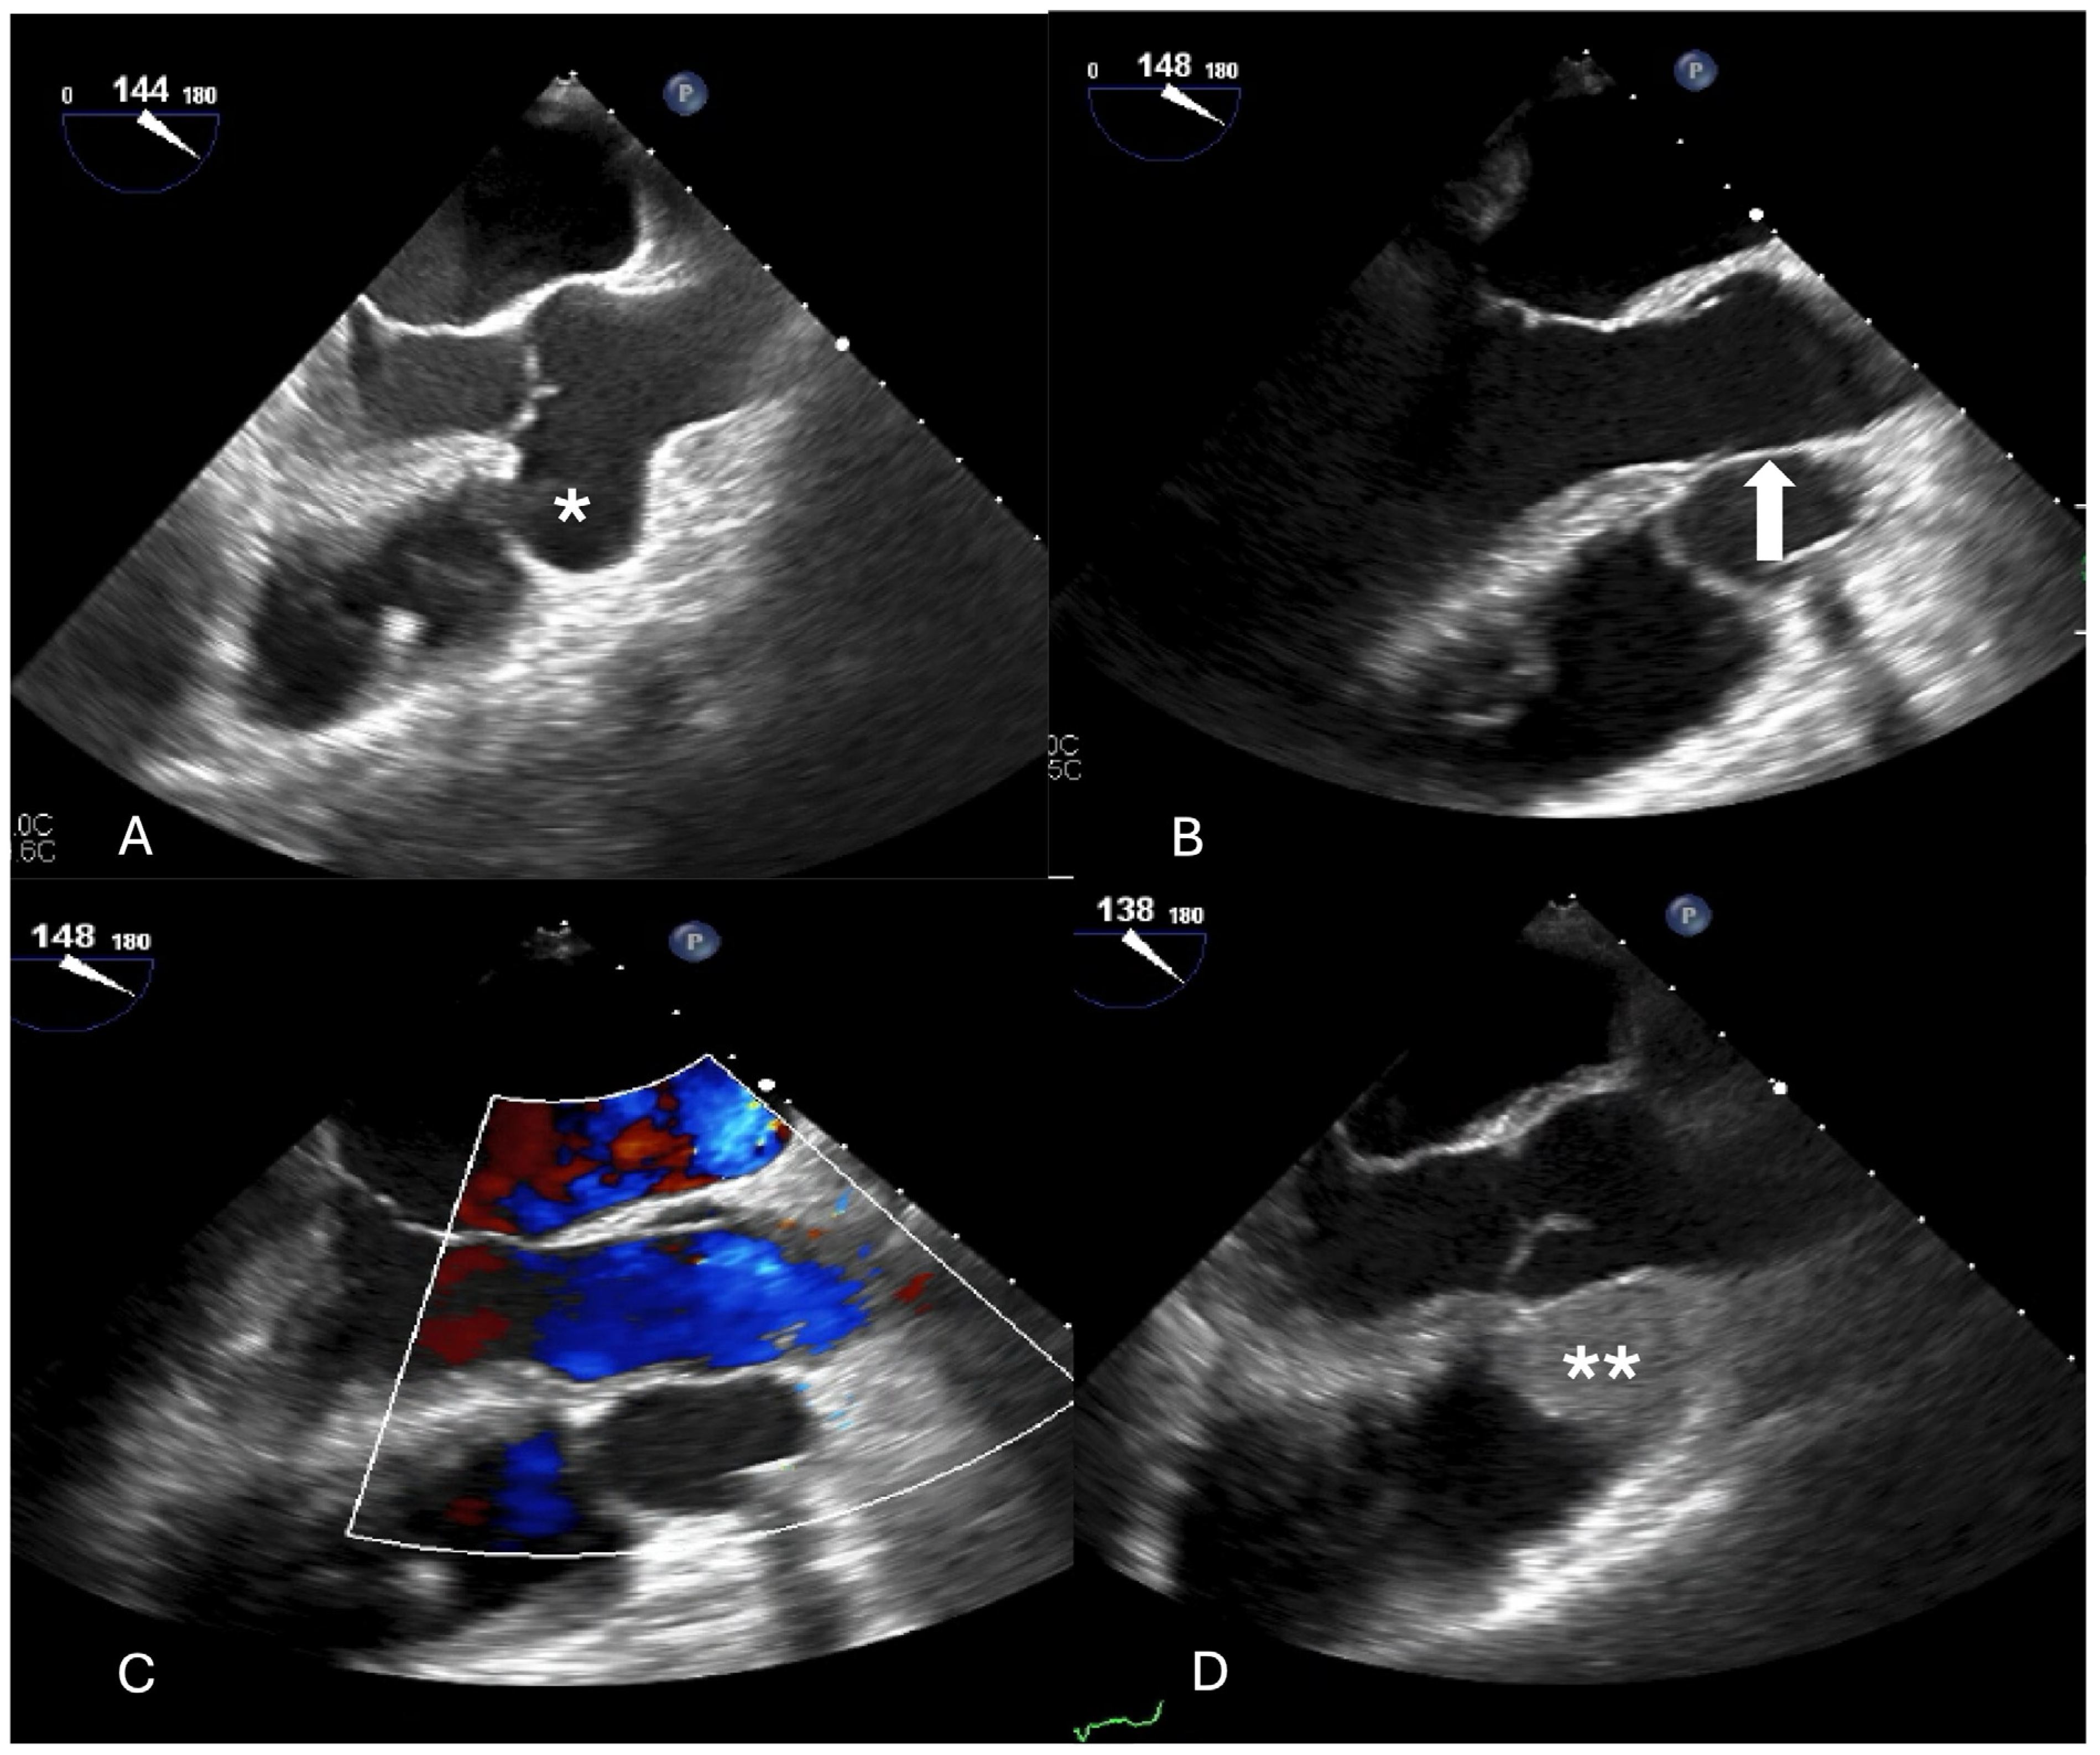

Inspection of the aortic root showed a tunnel-like communication between the right aortic sinus with a distal opening just under the anulus of the tricuspid valve. The aortic and myocardial tissue looked as pulled from each other with a tissue defect of about 1 cm. Inspection within the right atrium showed the distal orifice of the tunnel close to the anteroseptal commissure of the tricuspid valve. The corresponding part of the anulus was missing so that the patch was fixed to the rims of the defect but partially also directly to the tricuspid leaflet (Figure 2). On the aortic side, continuity between the aortic anulus and the aortic tissue was also reconstructed with a xeno-pericardial patch. Because of the diameter of 48 mm, composite-graft replacement was performed with a 25 mm Medtronic tube-valve graft in the classical open technique. Because of the weakness of the tissue close to the aortic anulus, valve-sparing repair after David was not thought to be a good option in this particular case. Weaning from cardio-pulmonary bypass was uneventful as the further recovery. The patient was discharged on postoperative day 6.

Figure 2. (A) Intraoperative echocardiography showing the ruptured sinus of valsalva aneurysm (white arrow). (B) Exposure of the aortic wall defect (SVA) (white **) below the right coronary ostium that has been detached. (C) Exposure of the defect with the rupture into the right atrium (the aneurysmatic sac is protruding into the right atrium) (yellow arrow). (D) Bentall procedure, the patch to reinforce the aortic anulus and the adjacent sinus can be seen under the sutures on the right.